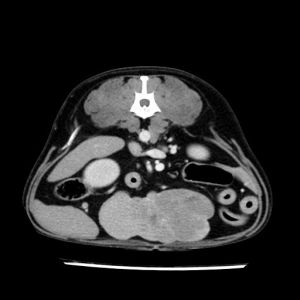

La lesione focale epatica , la ceus,la Tac e il chirurgo .